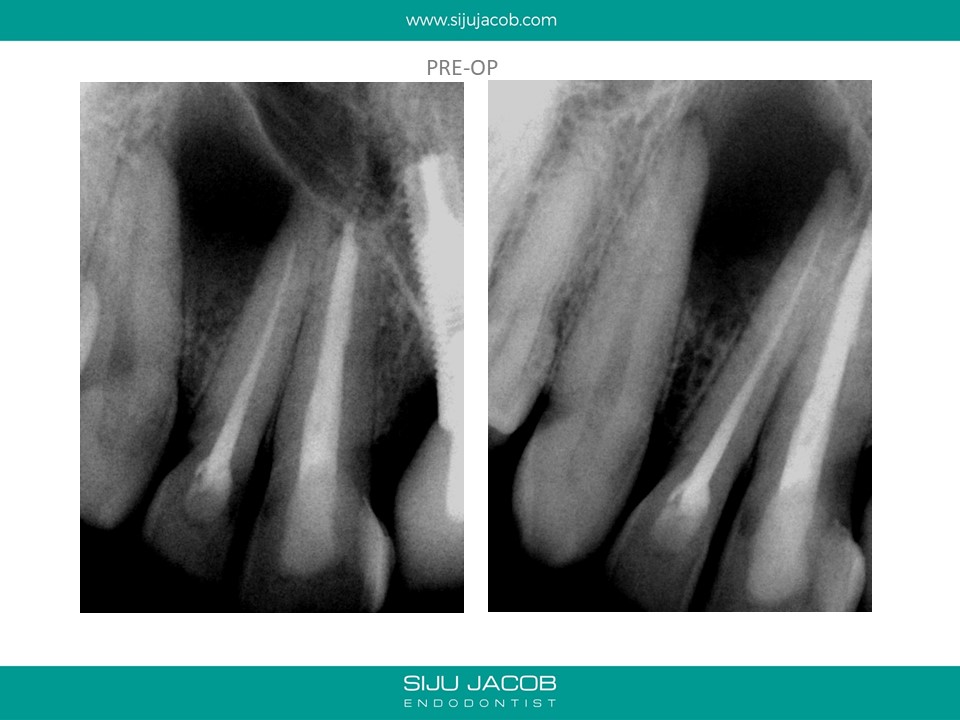

This patient was from The U.S. I re-treated a lateral incisor tooth of his while he was in Bangalore. He then went back to U.S. I received a mail from him two years later saying that the tooth we did was hurting. I thought that maybe, the lesion had recurred. I referred him to an Endodontist in the u.s who forwarded the radiograph to me. The lateral that I re-treated had healed well. It was an old central Incisor that had been treated much earlier that had fractured.